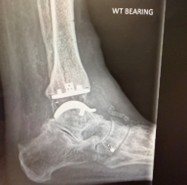

The latest data shows that ankle replacement survivorship and patient outcomes have improved significantly in recent years.

With modern implants, better surgical techniques, and refined rehabilitation pathways, patients are achieving excellent long-term mobility and comfort.

For others with more advanced arthritis, today’s ankle replacement techniques can restore movement and reduce pain while keeping the joint flexible something fusion can’t offer.